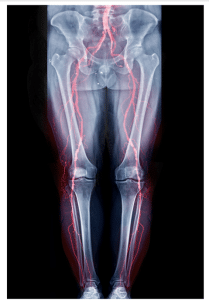

Venous thrombosis is one of the leading causes of morbidity and mortality in the United States and is one of the most frequent causes of presentation to an emergency department. Deep vein thrombosis (DVT) can cause thromboembolism, chronic venous insufficiency, and pulmonary embolism (PE), which can be fatal. Pulmonary Emboli, which are among the most preventable causes of death, are reported to develop initially in the lower extremities in about two thirds of patients. The development of PE is assumed to be as frequent as 10 to 50% if untreated, resulting from DVT. Prompt diagnosis and the initiation of anticoagulation or, in some cases, the placement of a Greenfield filter is extremely successful.

Compression ultrasonography as a method for diagnosing lower extremity DVT is proven to be equally sensitive and specific compared to other methods that use radiation or contrast agents. Conventional lower extremity Doppler studies, which evaluate the blood vessels in the entire limb, are done by ultrasound technicians and reported by radiologists. Still, these processes can take as long as two hours and slow diagnosis and treatment.

Patients with risk factors for DVT or PE should receive a diagnostic workup, which frequently involves using bedside compression ultrasound. Although contrast venography is the gold standard for DVT diagnosis, point of care ultrasound (POCUS) is being used in more EDs for lower extremity DVT assessment. Two main POCUS techniques are employed: the 2-point method, based on the compressibility of the common femoral vein (CFV) and popliteal vein (PV), and the 3-point method including the superficial femoral vein (SFV).

Current EDs preferentially employ a variation to the 2-point compression technique that targets high-risk regions for DVT, takes less than five minutes, and has comparable diagnostic sensitivity and specificity. A negative DVT compression ultrasound can help avoid the use of anticoagulant agents in patients suspected of having DVT. The 2-point compression method has been used in many studies and is widely accepted when used with pretest probability assessments.